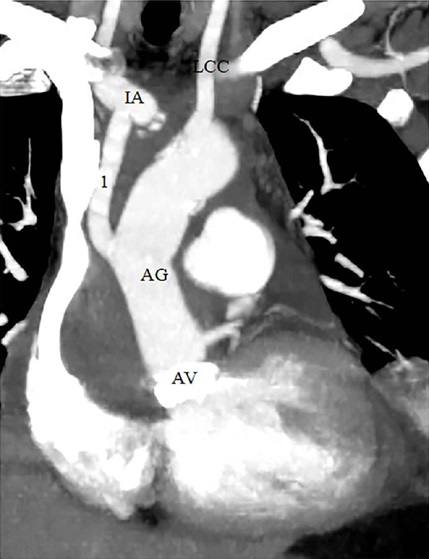

When the distal anastomosis was complete, ACP was discontinued. After protamine administration, the 8-mm graft was cut and oversewn with a double 5-0 polypropylene running suture. The total body and cerebral perfusion was maintained by IA during the entire procedure, except for the aortic arch repair. In aortic arch repair, extracorporeal circulation was reinstituted in an antegrade fashion through the ascending aortic graft via new aortic cannula for body and cerebral perfusion, and then the IA graft was anastomosed to the ascending aortic graft (Figures 2 and 3).

IA cannulation using 8-mm Dacron graft was successful in all patients. Details of the surgical procedures and operative times are presented in Table 2. There were no local complications, and there was no need to change cannulation site due to malperfusion or arterial injury in any of the patients. The postoperative outcomes of the patients are summarized in Table 3.